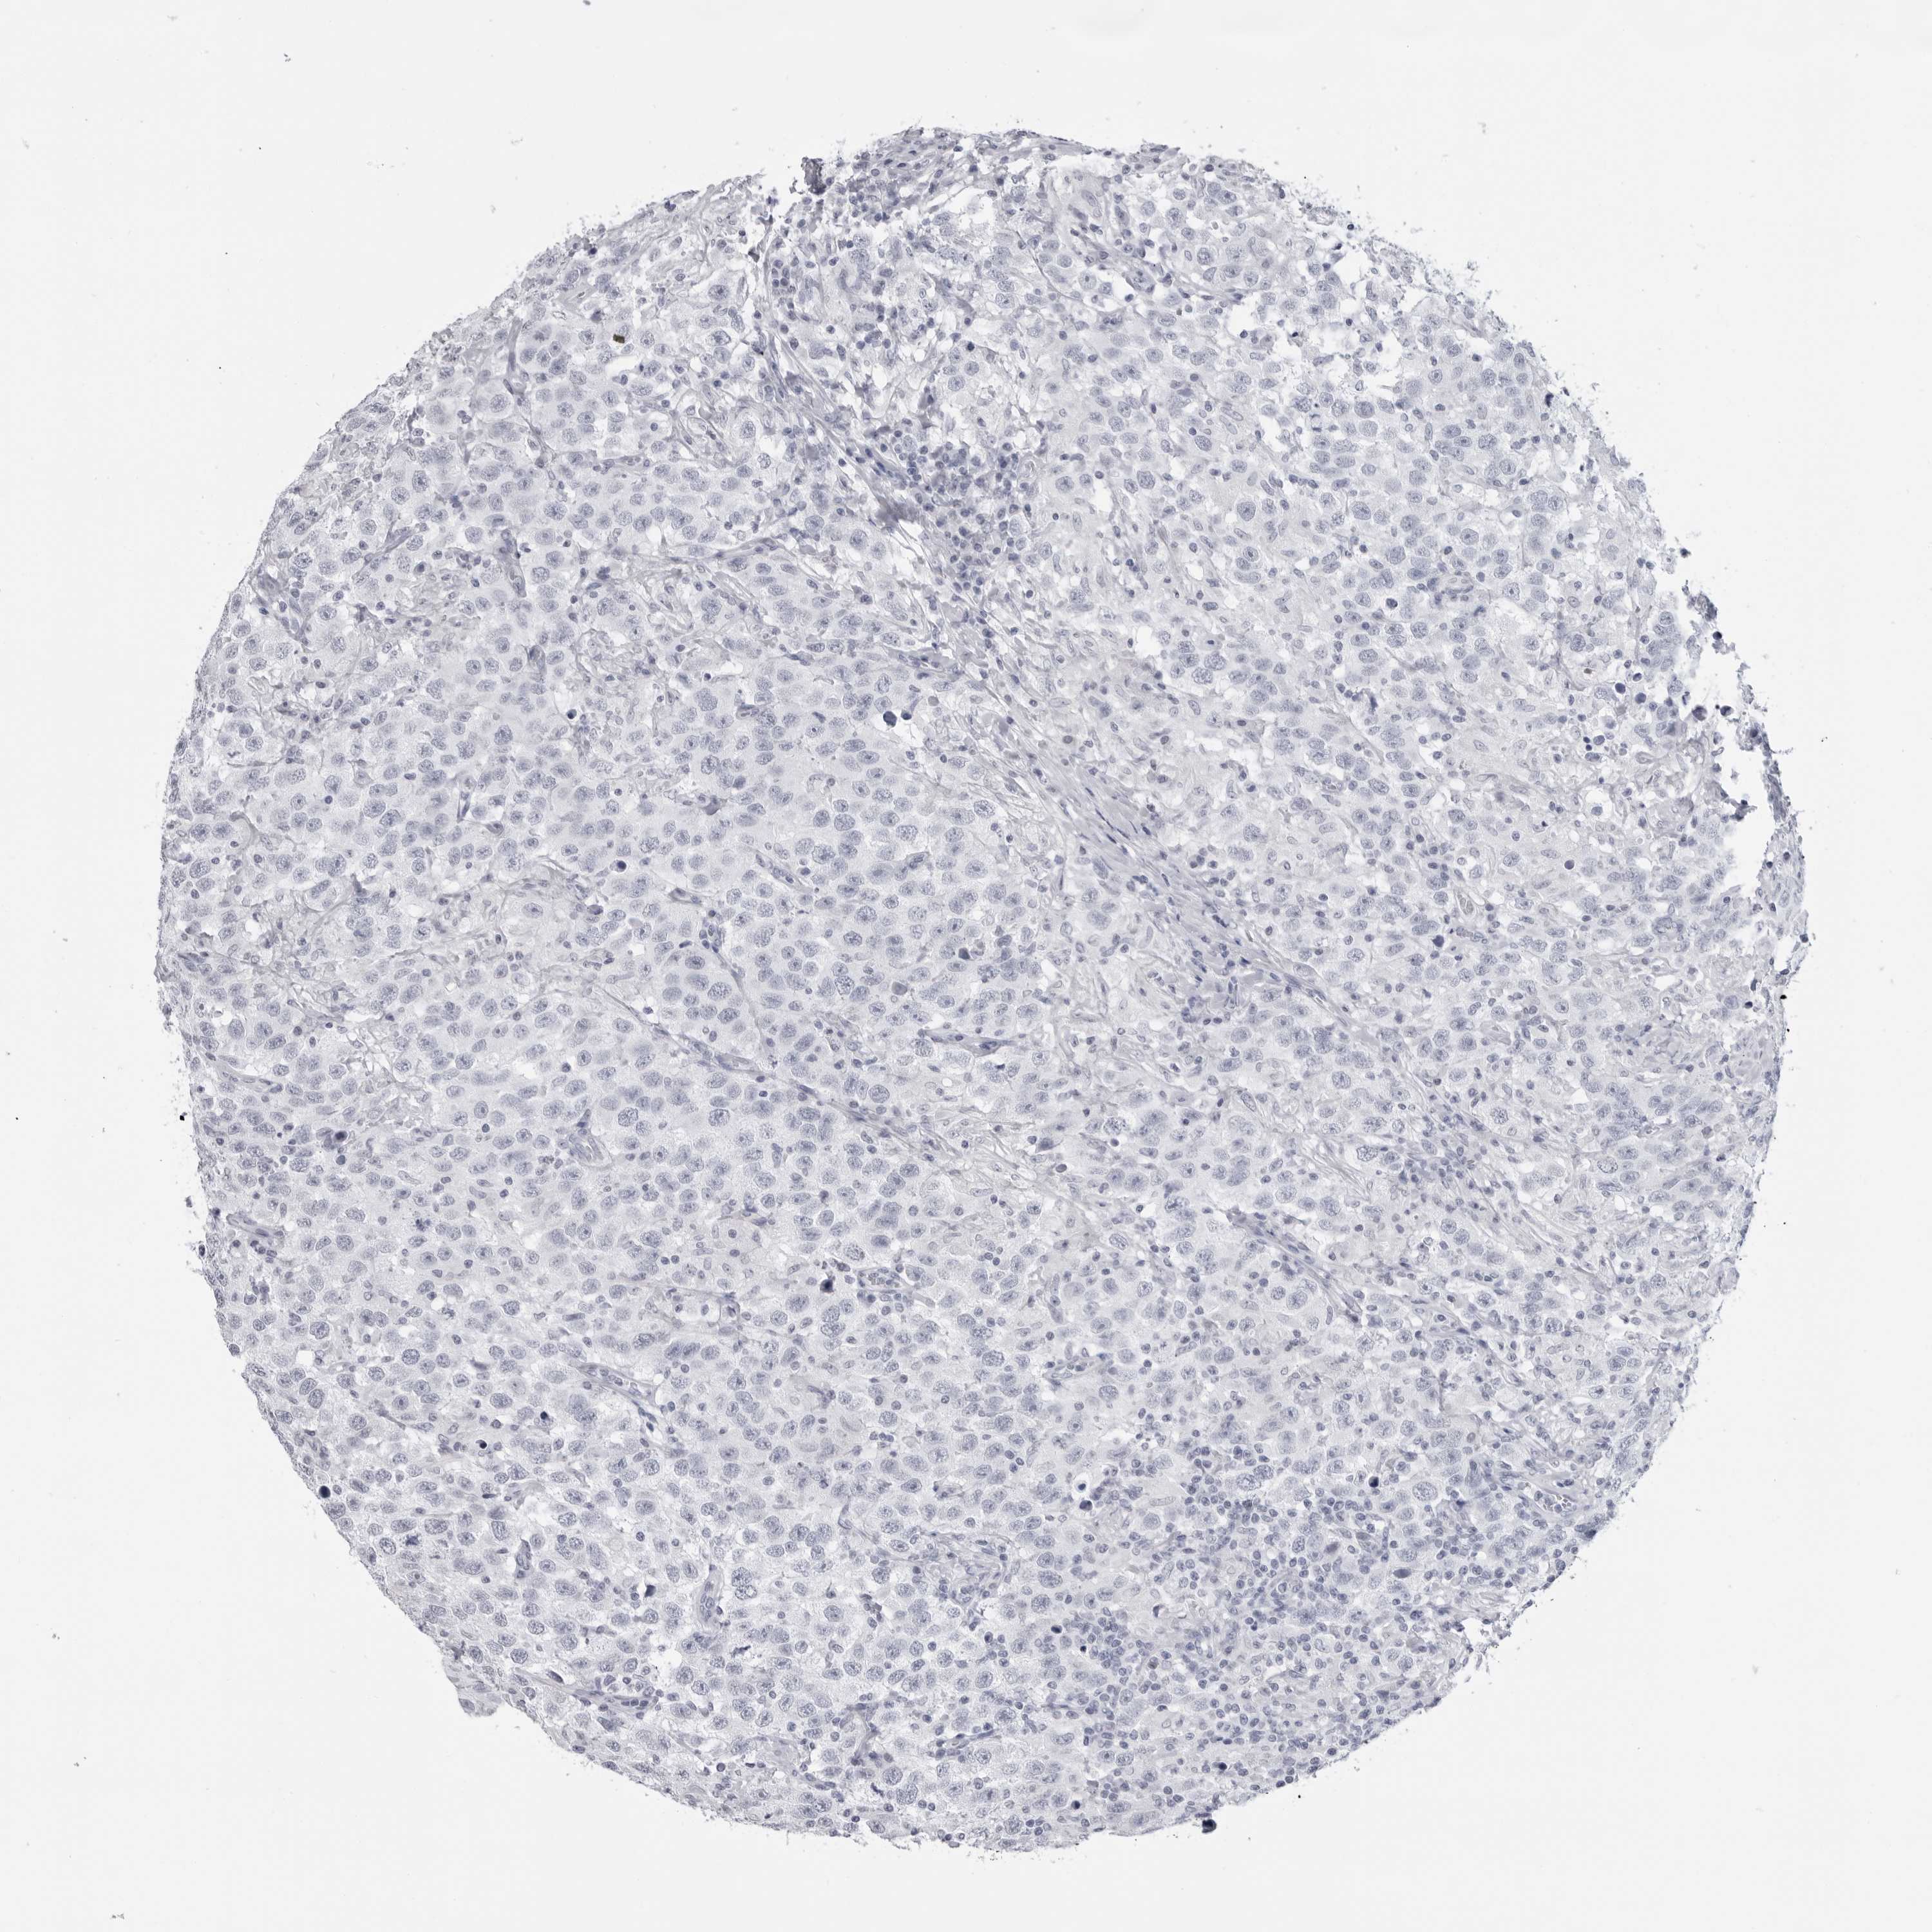

TESTIS CANCER - Protein expressioni

A mouse-over function shows sample information and annotation data. Click on an image to view it in a full screen mode. Samples can be filtered based on level of antibody staining by selecting one or several of the following categories: high, medium, low and not detected. The assay and annotation is described here.

Note that samples used for immunohistochemistry by the Human Protein Atlas do not correspond to samples in the TCGA dataset.

Antibody stainingi

Antibody staining in the annotated cell types in the current human tissue is reported as not detected, low, medium, or high, based on conventional immunohistochemistry profiling in selected tissues. This score is based on the combination of the staining intensity and fraction of stained cells.

Each image is clickable and will lead to virtual microscopy that enables deeper exploration of all samples and also displays staining intensity scores, fraction scores and subcellular localization as well as patient and tissue information for each sample.

Antibody HPA046875

Seminoma, NOS

Carcinoma, Embryonal, NOS